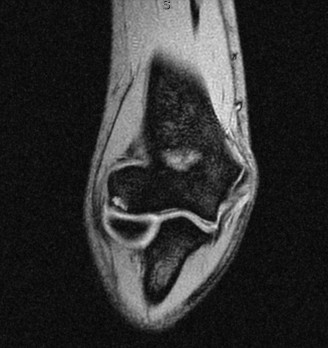

You send the patient for an MRI, which is shown in Figure 2–66.

Figure 2–66

Based on the clinical examination and imaging, what is the most likely etiology of the patient’s symptoms?

The correct answer is (C). The patient’s clinical examination findings of isolated

weakness in external rotation and atrophy of the infraspinatus muscle point to suprascapular nerve entrapment at a location past the exit point for the branch to the supraspinatus muscle. Also, MRI reveals a posterior labral tear with a paralabral cyst that is compressing the suprascapular nerve at the spinoglenoid notch. Choice A, while fitting with the patient’s clinical examination, does not fit with the MRI showing paralabral cyst. Choices B and D are incorrect because entrapment of the suprascapular nerve at the suprascapular notch by scapular body fracture or by the transverse scapular ligament (more common) would lead to weakness/atrophy in both supraspinatus and infraspinatus muscles as the suprascapular notch is proximal to the nerve branch point to the supraspinatus muscle.